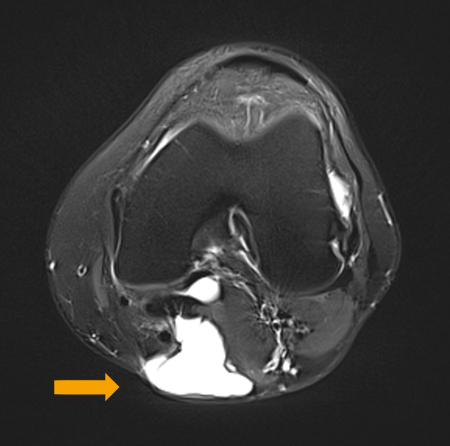

Um estudo demonstrou que os cistos poplíteos se desenvolvem por falta de um suporte anatômico externo.[1] Essa área é encontrada entre as duas expansões do músculo semimembranoso e do gastrocnêmio medial.[Figure caption and citation for the preceding image starts]: RNM mostrando cisto no intervalo do gastrocnêmio medial e semimembranosoDo acervo do Dr John D. Kelly IV; usado com permissão [Citation ends].